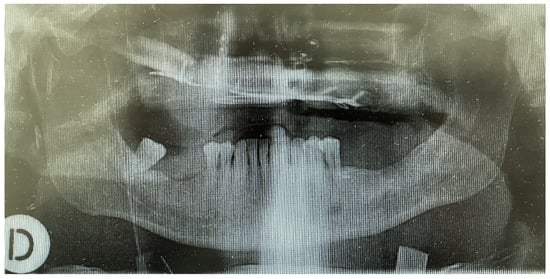

2. Case Presentation